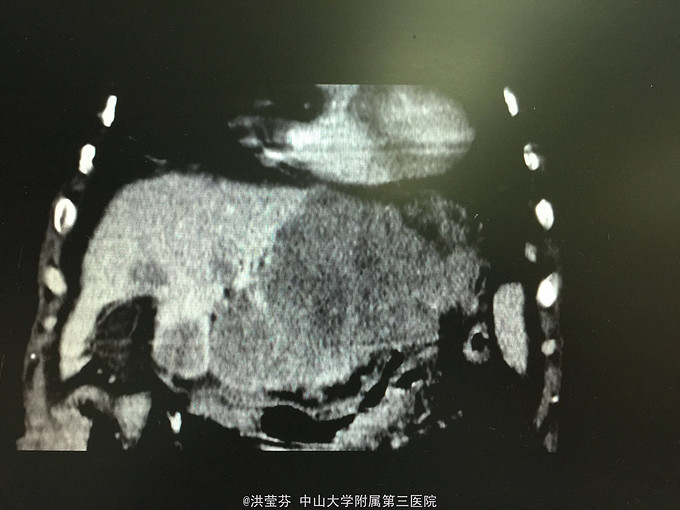

查体:上腹部轻压痛,无反跳痛。 辅助检查:上腹部CT增强提示:肝S2/3/4段恶性肿瘤,肝内多发子灶,肝左静脉及门静脉左、右支受侵;腹腔多发转移瘤;肝门部、腹膜后多发肿大淋巴结;门静脉海绵样变;少量腹水。胸部CT提示:1、双肺多发小结节,结合病史,考虑转移瘤;纵膈、双侧肺门多发肿大淋巴结。2.双肺炎症;左侧胸腔少量积液。CA125 555.1IU/nl,CA199 1093.5IU/nl。

诊断考虑胆管细胞癌可能性大,予完善肝穿刺,活检病理示:符合中分化腺癌,胆管细胞癌可能性大。免疫组化结果示:Hep(-),CK(+),CK19(+),CEA(-),CDX-2(-),DK20(-),Ki 67(约15%),TTF-1(-)。诊断明确肝内胆管细胞癌,IV期,无明显化疗禁忌,予GP方案化疗,辅以护胃、护肝、止吐等治疗。